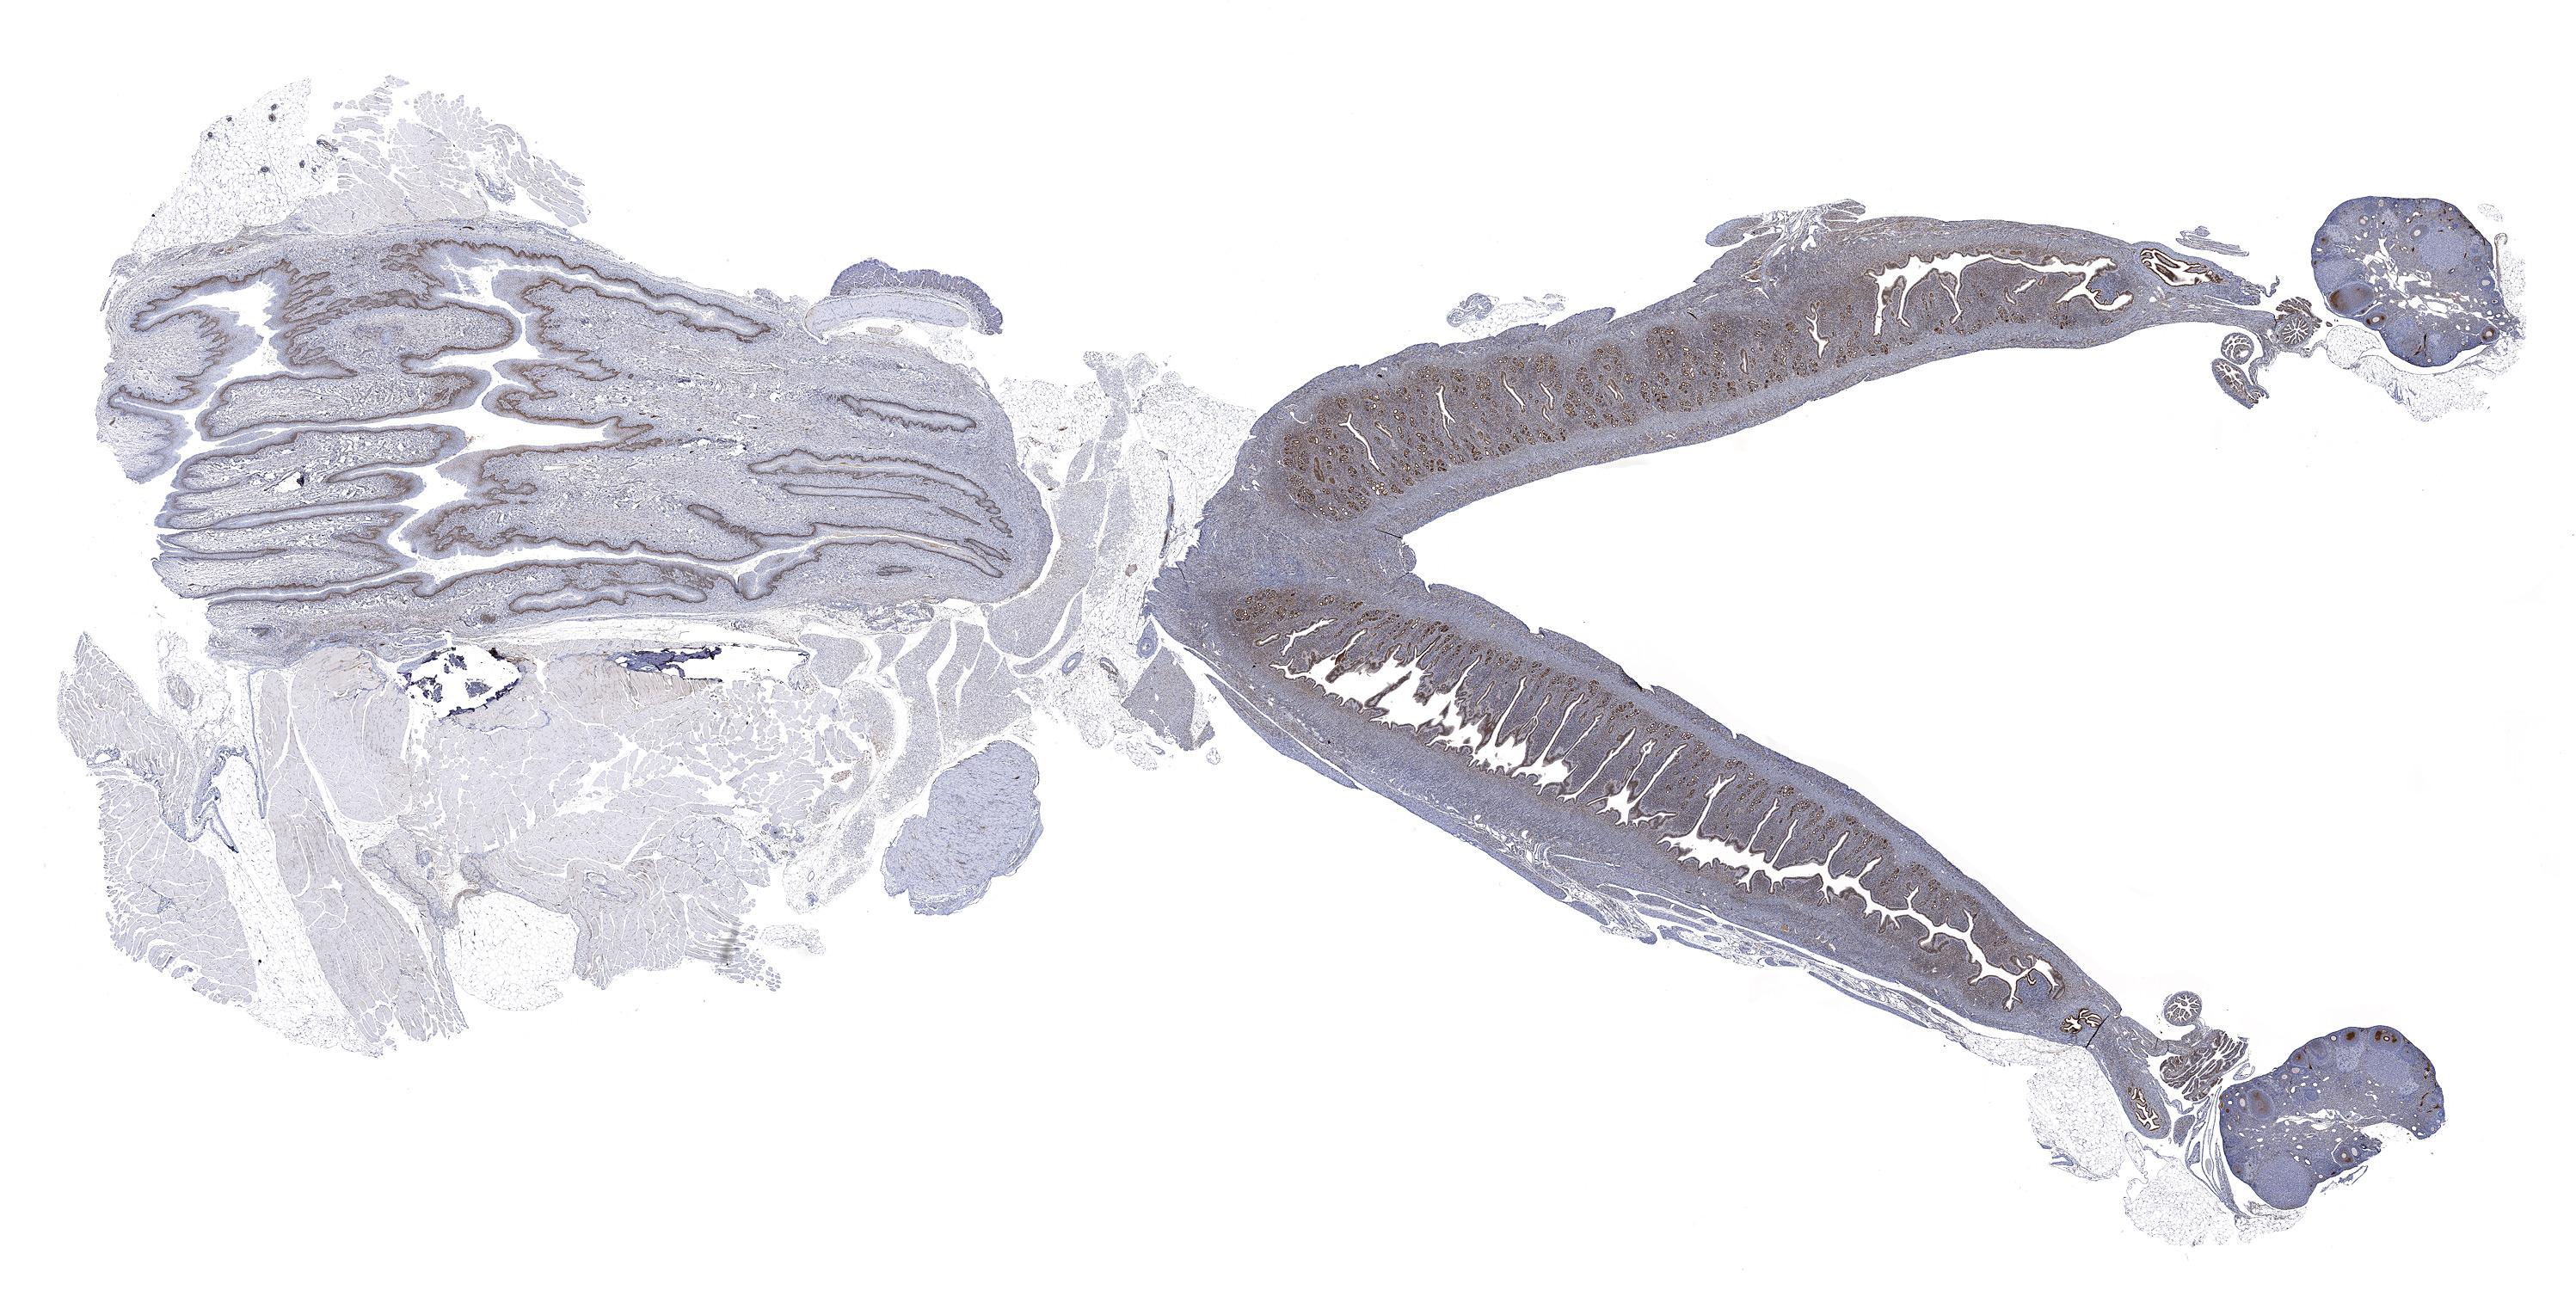

Estrogen Receptor Alpha: Immunoperoxidase staining of formalin-fixed, paraffin-embedded mouse female reproductive tract showing nuclear staining throughout the uterus, cervix, and vagina